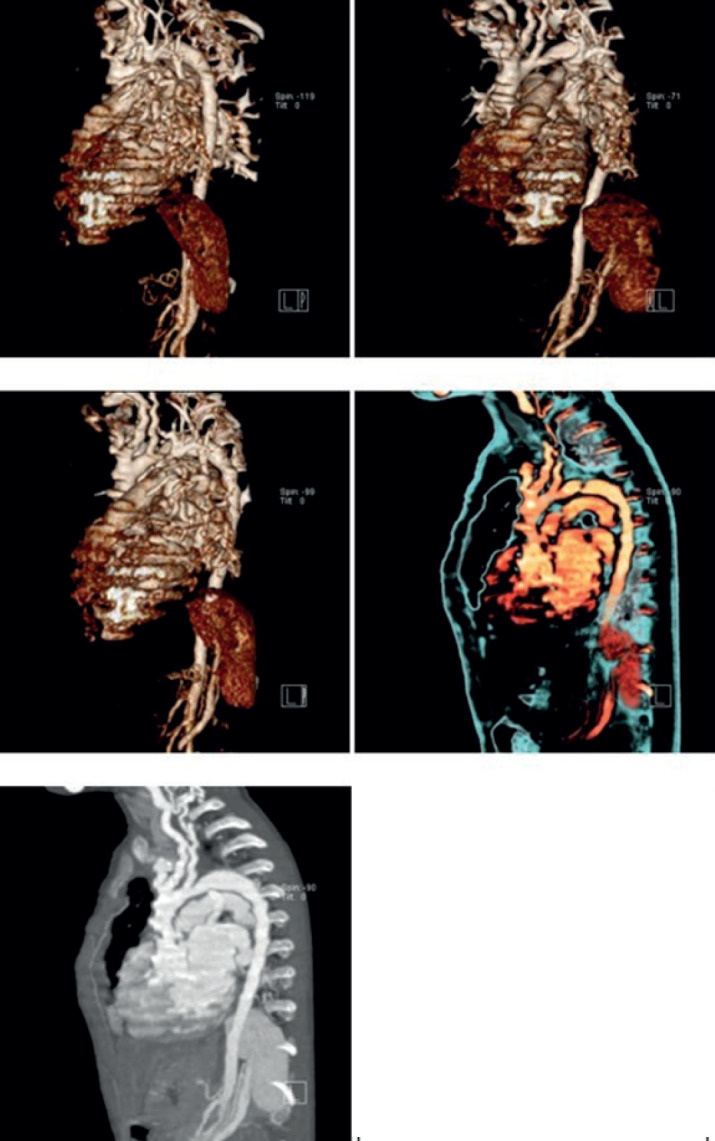

Background: Arterial tortuosity syndrome (ATS) is a rare congenital connective tissue disorder characterized by elongation and generalized tortuosity of the major and distal arteries, including the aorta. Clinically syndrome is associated with hyperextensible skin and hypermobility of joints.

Objective: Here we present a three-year-old boy who was referred to our center for investigation of incidental murmur; but subsequently he was found to have ATS.

Results: A 3-year-old boy with lax joints and hyper flexibility of the skin was found to have severe tortuosity of the great vessels along with critical aortic coarctation. Diagnosis and management aspects have been discussed. This review delves into a variety of strategies that could be harnessed to enhance radiology diagnostic services, thereby better-serving stroke patients in multidisciplinary hospital settings. It sheds light on the current hurdles in the optimization of stroke management, discussing them in detail. This article also explores the application and significance of Process Mapping in streamlining workflow for stroke management in hospitals, providing insights into its benefits, challenges, and future implications. Furthermore, the potential of Artificial Intelligence (AI) and Machine Learning (ML) in refining stroke management processes is also analysed and discussed.